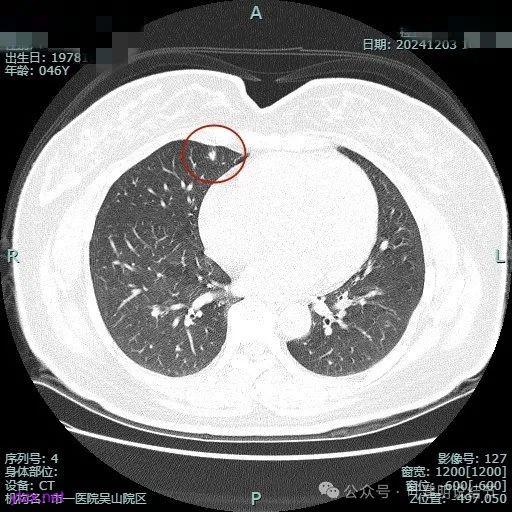

时间很快到了2025年3月,结友又来我门诊复查,我还以为她在别处开了刀了呢,结果并没有,说是与家人商量后决定吃中药三个月看看能不能好。我们来看看再复查的情况,中药有没有起作用:

总体感觉三处病灶边缘的淡磨玻璃成分好转不太明显了,实性成分较前略显致密点,大小与形态是说不上显著变化的。所以有几点可以肯定:1、消炎没有效;2、中药没有用;3、考虑多原发肺癌,且为浸润性腺癌可能性大些,得手术!